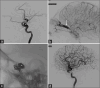

Figure 3

Images from the cerebral angiogram depicting pre- and post-embolization/coiling status of the carotid-cavernous fistula (CCF). (a) Arterial phase image demonstrating the direct communication (white arrow) between the cavernous segment of the internal carotid artery (ICA) and the cavernous sinus (white asterisk). (b) Early venous phase image showing filling of the superior ophthalmic vein (SOV) (white arrow) and other orbital veins with flow away from the cavernous sinus, indicating increased pressure and proptosis due to the direct fistula. (c) Unsubtracted image during coil deployment (white asterisk) in the cavernous sinus to interrupt the ICA-CS communication. (d) Check angiogram postcoiling, demonstrating complete closure of the CCF with no flow to the cavernous sinus or filling of the SOV